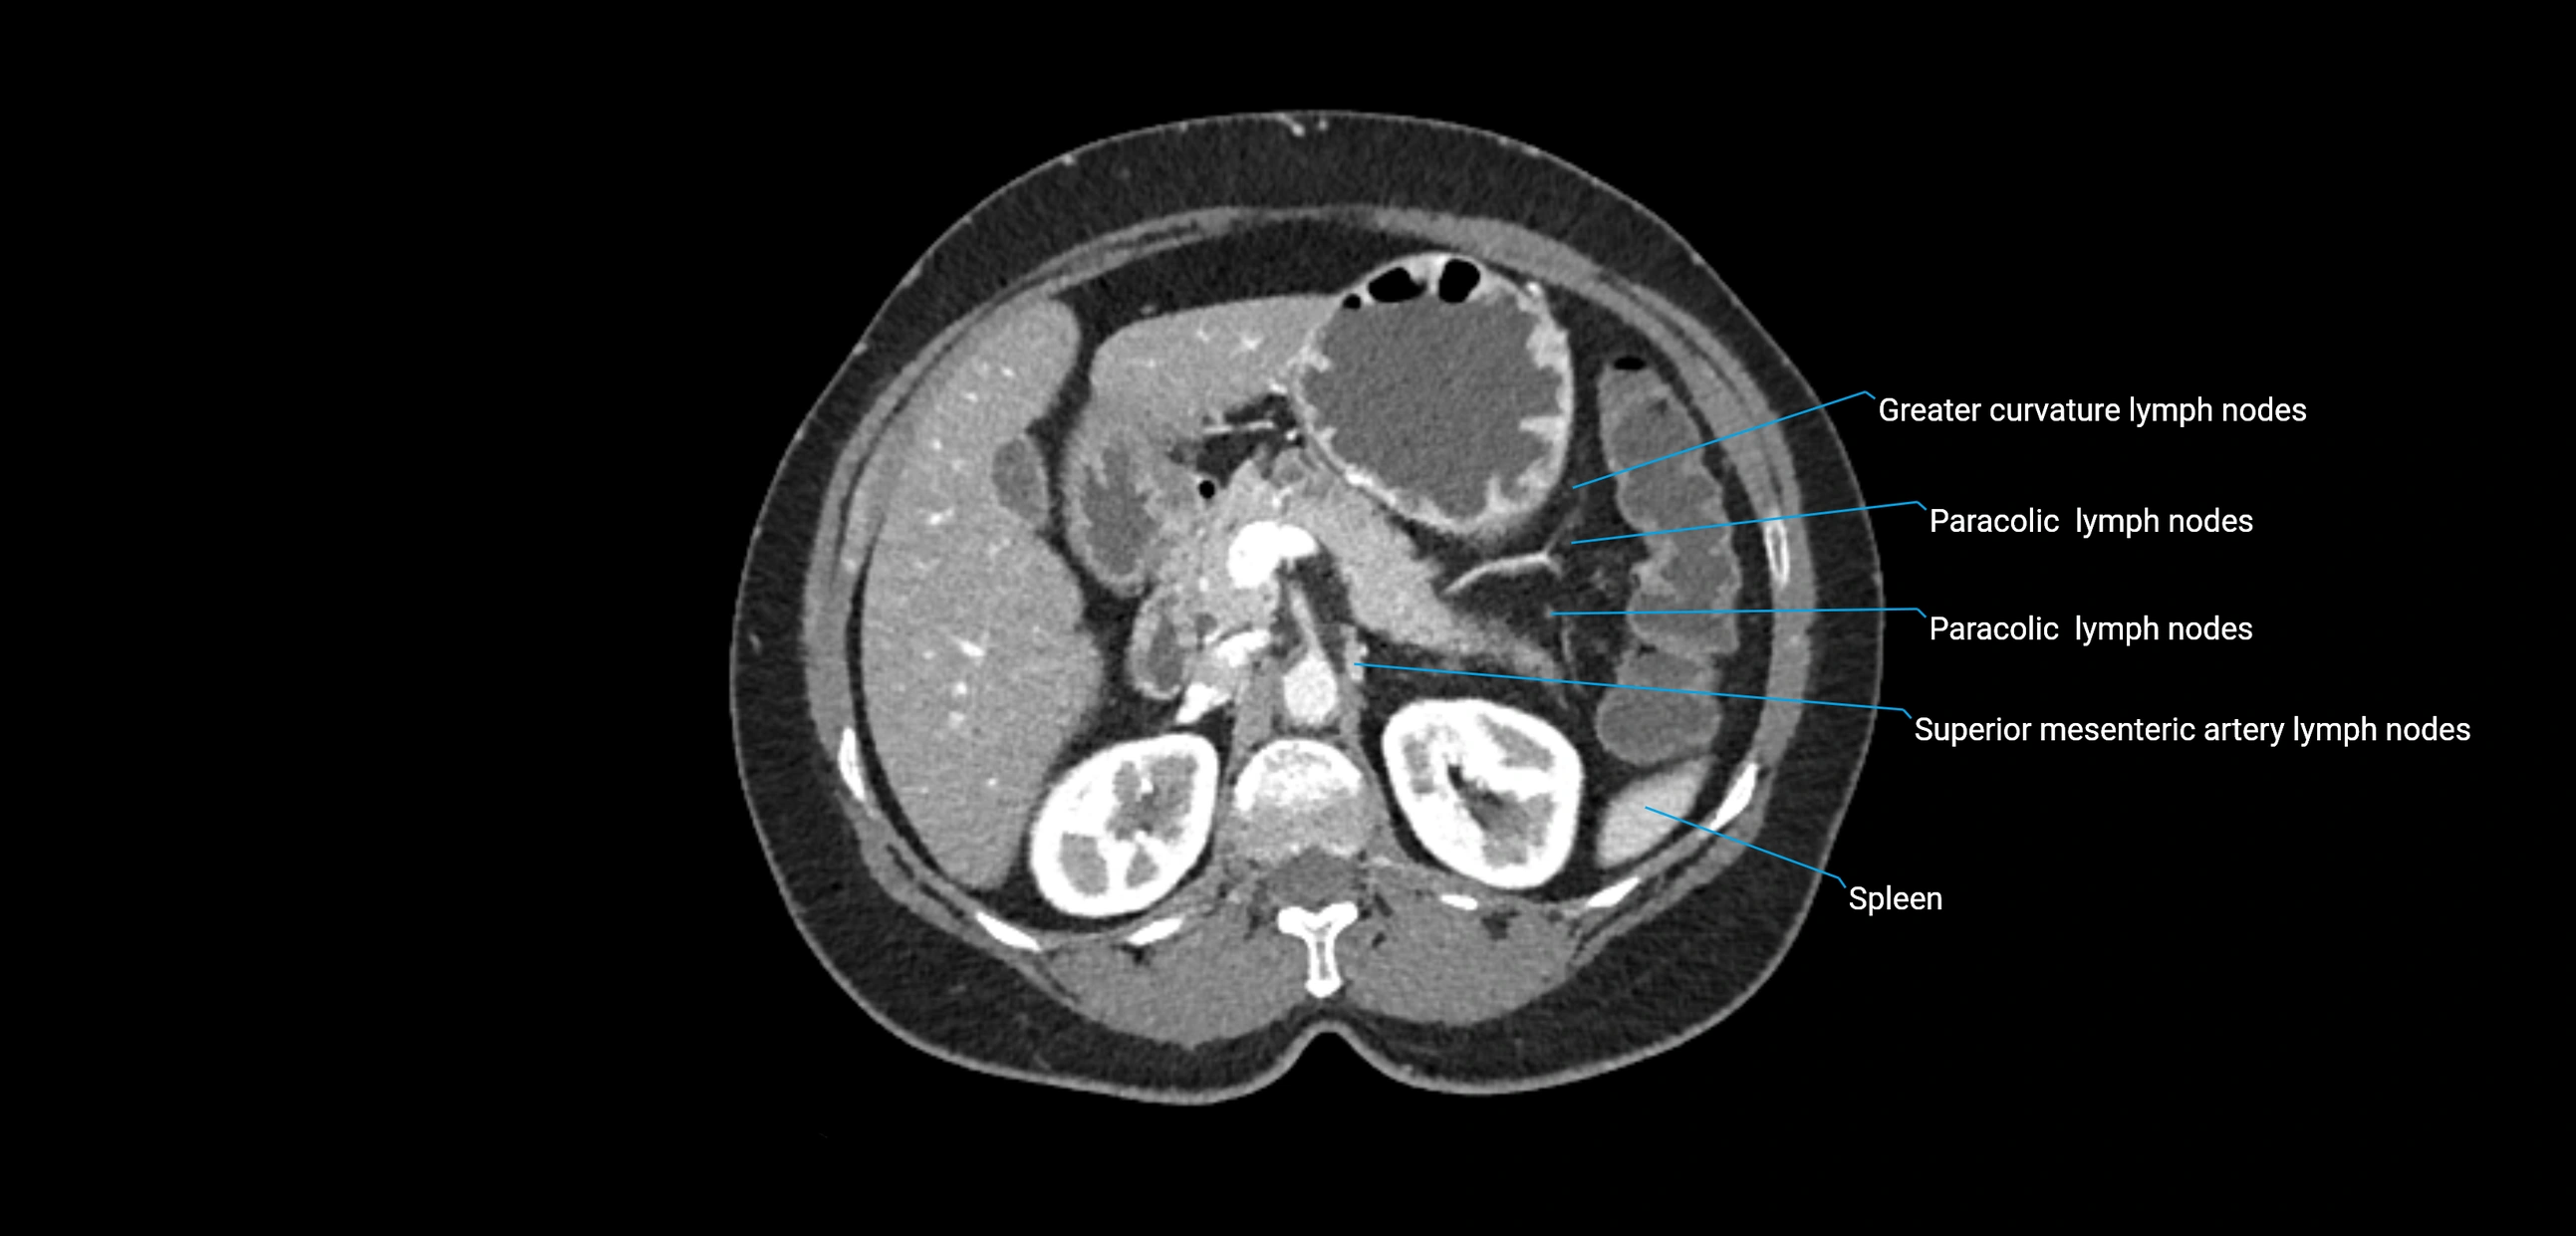

CT Appearance

CT Pre-Contrast:

• Nodes appear as soft-tissue density nodules adjacent to the aorta and IVC

• Calcification may be seen in chronic infections (e.g., tuberculosis)

CT Post-Contrast:

• Normal nodes enhance homogeneously

• Malignant nodes may show heterogeneous enhancement, central necrosis, or conglomerate formation

• Size >1 cm short axis is suspicious, though morphology and distribution are equally important